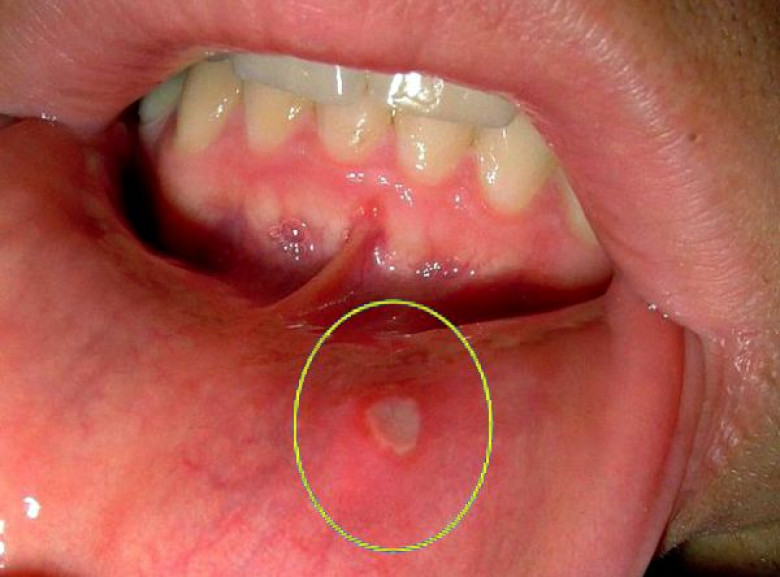

Բերանի խոռոչի թեթև կարմրությունը հանդիսանում է ստոմատիտի առաջին նախանշանը: Ժամանակի ընթացքում ավելի ուռում ու այտուցվում են: Եթե չսկսել այս շրջանում բուժումը, կարմրությունը կփոխարինվի խոցոտումներով՝ ոչ մեծ չափերի, օվալ կամ կլոր ձևով, մոխրագույն կամ սպիտակ գույնով, կարմիր երիզով և պատված թաղանթով: Եվ շուրջը գտնվող հյուսվածքը բացարձակապես առողջ է: Լեզուն նույնպես շատ ցավոտ է, և դժվարացնում է սննդի ընդունումը:

Խոցերը հիմնականում առաջանում են եզակի՝ սա թեթև ձևն է: Կա նաև բարդացած ձև, երբ մի քանի խոցեր՝ տարբեր ձևի և չափերի միավորվում են: Խոցերի առաջացումը զուգորդվում է ջերմության բարձրացմամբ, ավշային հանգույցների բորբոքմամբ, ինքնազգացողության վատացմամբ, գլխացավով, ախորժակի կորուստով, փորկապությամբ և այլ ախտանիշներով:

Աֆթոզ ստոմատիտ-Պատճառ կարող են հանդիսանալ ՍԱՀ-ի հիվանդությունները, ալերգիկ ռեակցիաները, վիրուսները, ռևմատիզմը, ժառանգականությունը: Բերանի խոռոչում հայտնվում են 3-5 մմ խոցեր մոխրասպիտակավուն գունավորմամբ, միայնակ կամ բազմակի, վատ ինքնազգացողություն, ջերմության բարձրացում և ցավեր խոցոտված հատվածներում: Կարող է լինել սուր և անցնել խրոնիկական ռեցիդիվող ստոմատիտի: